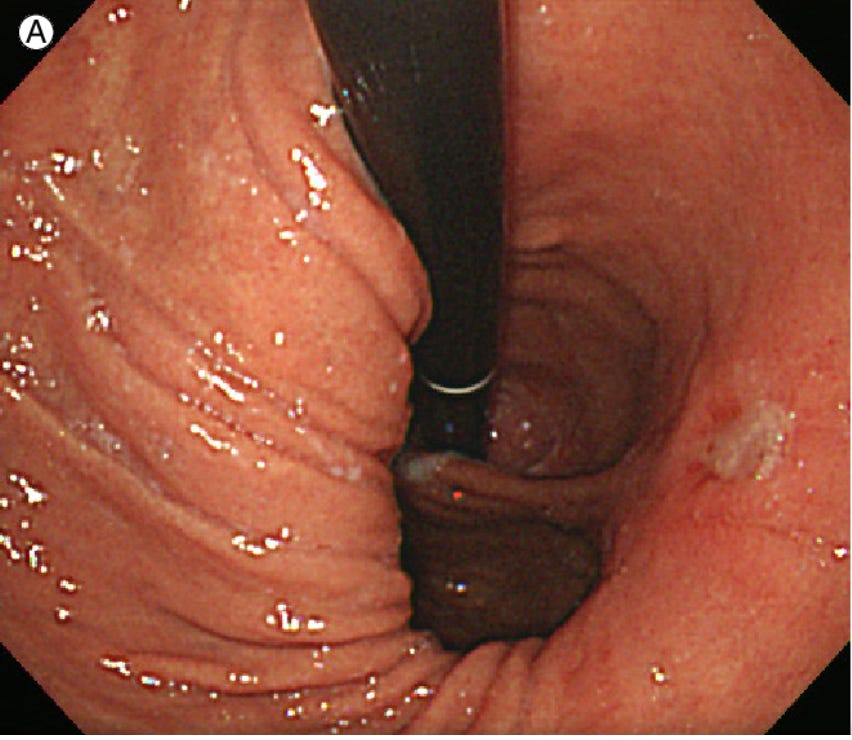

On endoscopy, we look for the gastro-oesophageal junction sitting more than 2cm above the diaphragmatic impression. We also use the Hill classification, viewing the valve from below in retroflexion.